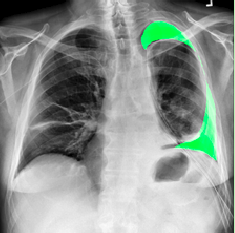

Our model is showing promising results as we can see the masks predicted by the model in figures 8(a) 8(b) 8(c) match closly to the real annotation. Our Dice score and IoU score are 84.3 and 82.6 respectively. Both of these metrics are used to indicate the similarity between images. And in figures 9(a) 9(b) 9(c) 10(a) 10(b) 10(c) we can see the results are very good and insightful. Both Dice score and IoU indicates that model is strong. Dice score and IoU both are positively correlated. It means if one say a model is strong then other will also support the decision. Using ResNet as backbone in U-net architecture helps converse the model fast and improves the results. The implementation is also easy in Keras. There are other metrics also but these metrics are considered best to test similarity between two images.

Refer to caption

(a) Input image

(b) Image with predicted mask

(c) Real Annotation

Figure 9: Patient 2